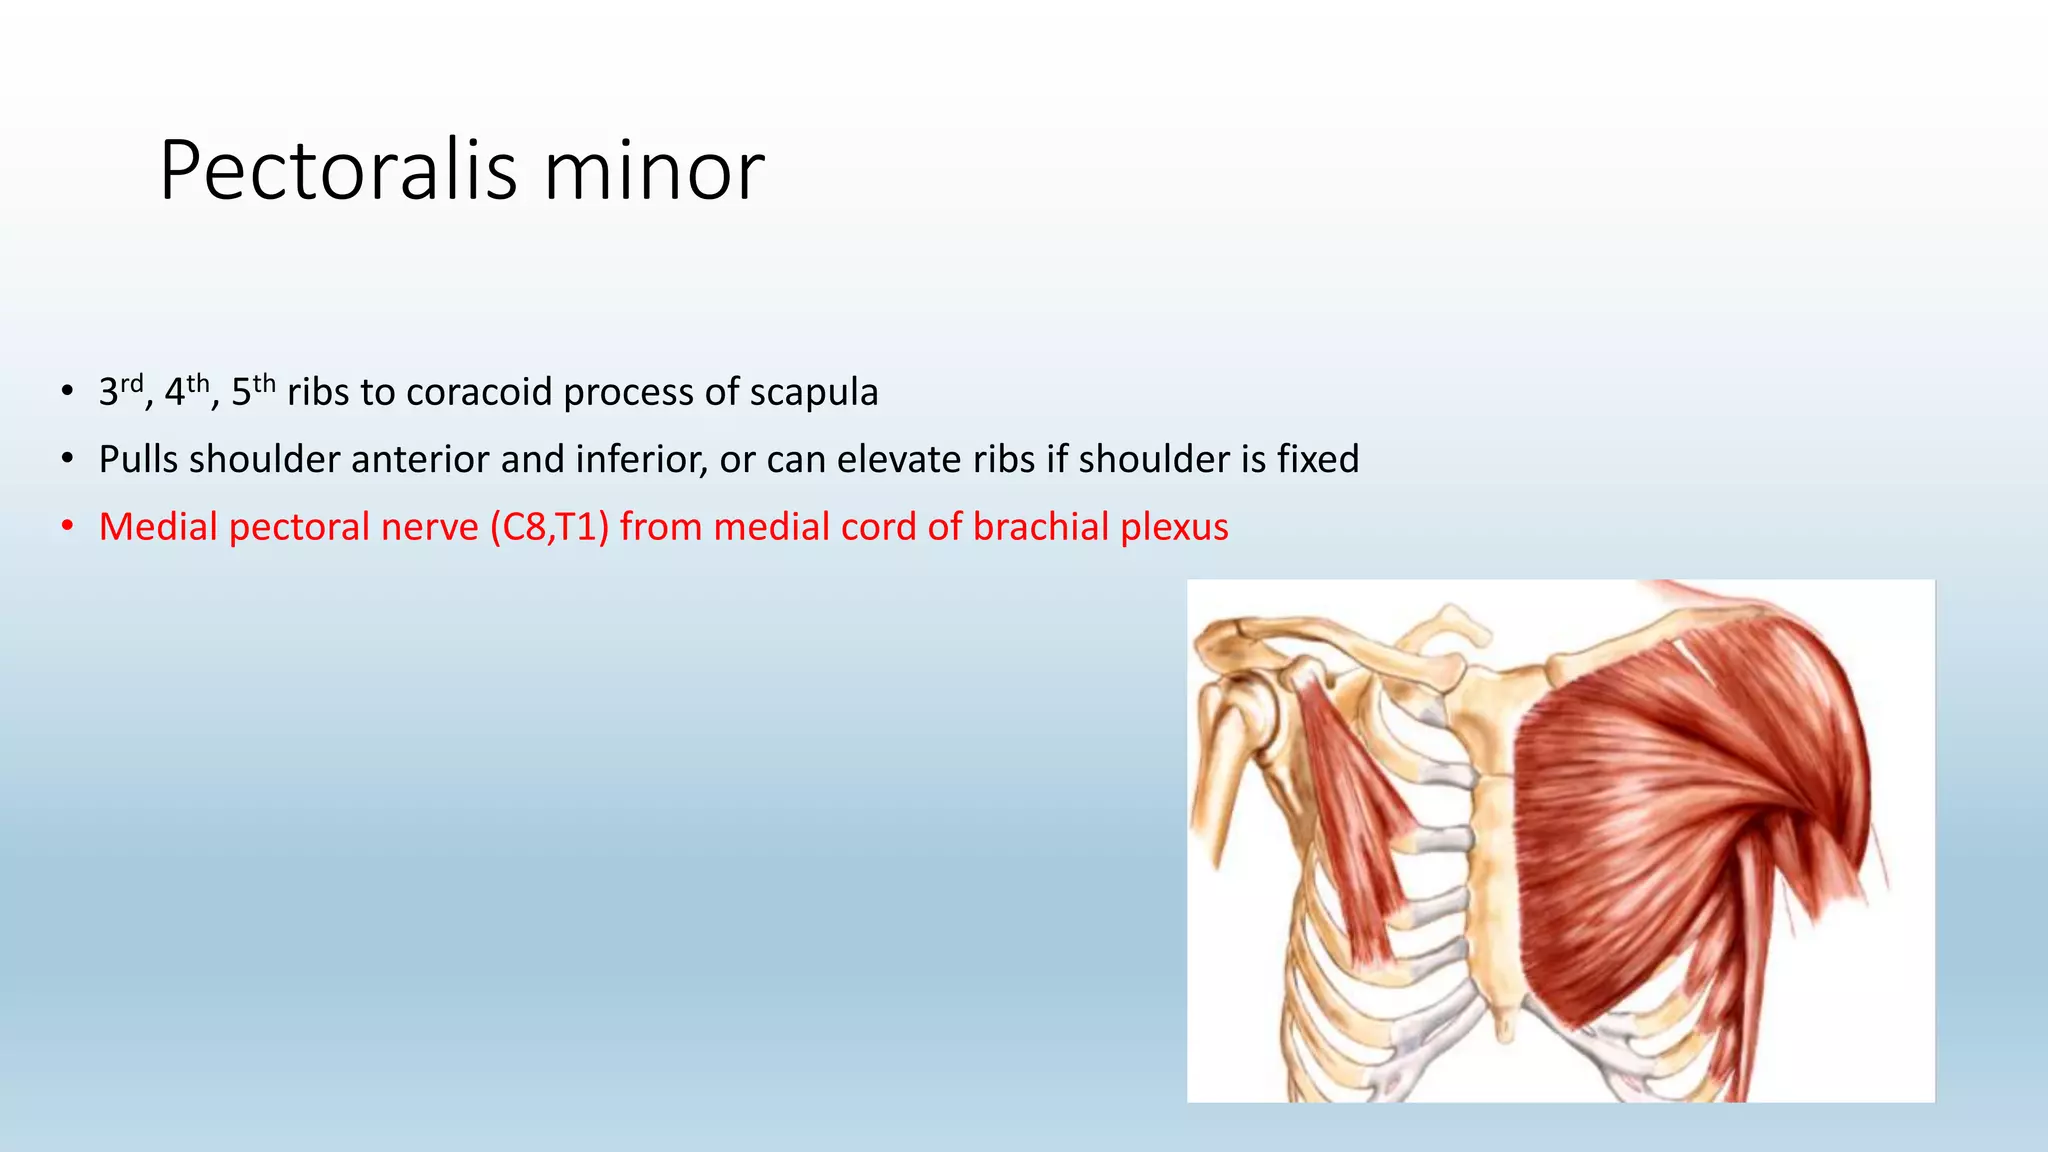

The document summarizes an anatomy revision session on the upper limb. It discusses various muscles of the upper limb including their origins, insertions, innervations and functions. Key muscles covered include the pectoralis major and minor, serratus anterior, deltoid, biceps brachii, brachialis, coracobrachialis, and triceps. It also discusses the rotator cuff muscles and muscles of the forearm including flexor carpi ulnaris and radialis. The session aims to help students identify upper limb muscles and understand their relations to nerves.